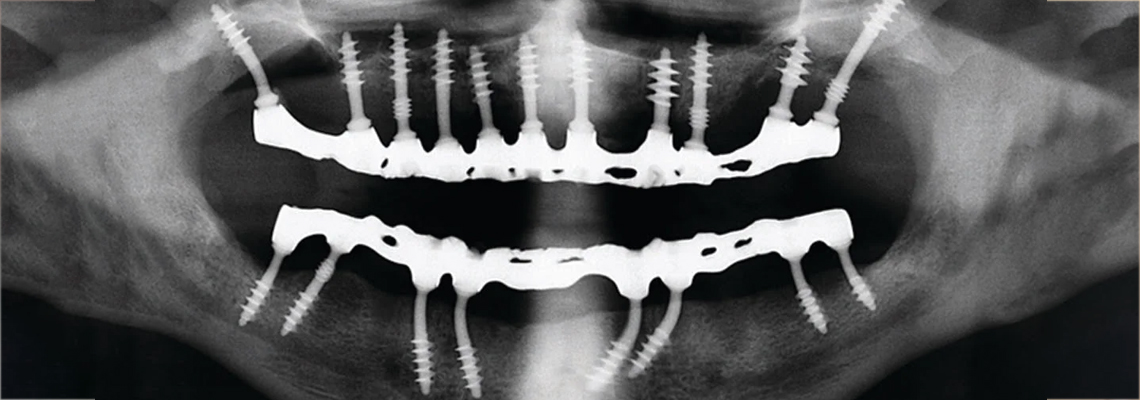

When my dentist told me I needed a bone graft before I could even think about dental implants, my heart sank. The explanation sounded complicated, expensive, and painfully slow. Months…